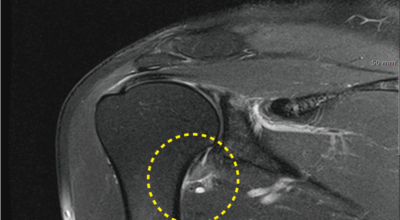

오십견이란 어깨의 통증과 어깨관절의 운동범위 제한을 특징으로 하는 질환으로 특히 50대 이후에 많이 발생함으로 오십견이라 이름이 지어졌으며 어깨관절이 얼어붙었다는 뜻으로 동결견(frozen shoulder)이라고도 합니다. 어깨관절의 운동성이 소실되기 때문에 옷 입기, 머리 감기, 물건 들기 등의 일상생활에 많은 어려움이 유발되며 통증에 의하여 잠을 못자는 경우도 대개 발생하게 됩니다.